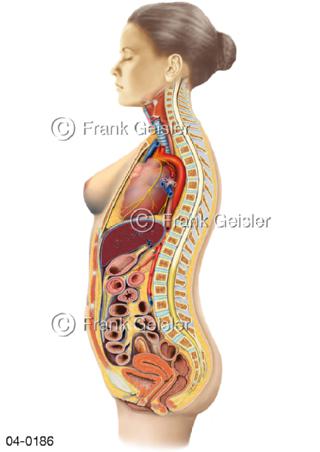

Bildergalerie Topografie Organe

Bilder zur topografischen Anatomie, die Lage der Organe und die Strukturen nach ihren räumlichen Lagebeziehungen zueinander, Übersicht der inneren Organe im Kopf und im Rumpf, Topografie der Organe im Brustraum (Thorax) und im Bauchraum (Abdomen)